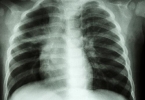

胸口痛可能由肌肉拉伤、胃食管反流、心绞痛、胸膜炎、肋间神经痛等原因引起,可通过休息调整、药物治疗、手术干预等方式缓解。

冠状动脉供血不足导致的心绞痛多表现为胸骨后压榨性疼痛,可能放射至左肩或下颌。发病与动脉粥样硬化、血管痉挛等因素相关,常因劳累或情绪激动诱发。确诊需心电图和冠脉造影检查,急性发作时可舌下含服硝酸甘油片,长期管理需使用阿托伐他汀钙片等调脂药物。出现持续胸痛伴冷汗需警惕心肌梗死。

胸膜炎症刺激可引发尖锐性胸痛,呼吸或打喷嚏时加重,多伴随咳嗽、低热。病因包括肺炎、结核或自身免疫性疾病。治疗需针对原发病使用注射用头孢曲松钠等抗生素,疼痛明显时可短期服用布洛芬缓释胶囊。胸腔积液量多时需穿刺引流,恢复期应避免剧烈咳嗽以防胸膜粘连。